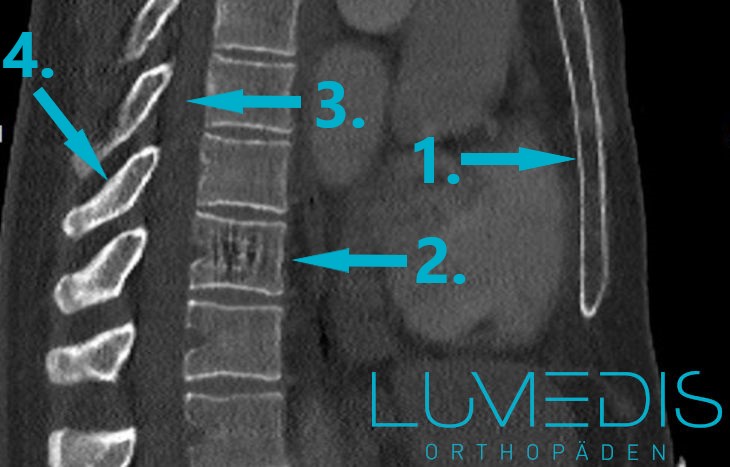

CT eines Wirbelbruchs der LWS seitlich